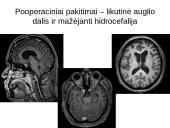

Pooperaciniai pakitimai – likutinė auglio dalis ir mažėjanti hidrocefalija